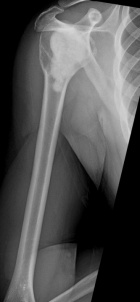

28 y/o male eight years s/p curettage and cementation for a right proximal humerus lesion found to be an aggressive enchondroma; presents with increasing R shoulder pain, worse with activity and direct pressure

PE: Healed surgical scar R shoulder, no TTP, mild edema, no LAN; FAROM, neurovascularly intact, 5/5; pain reproduced with shoulder extension and pulling